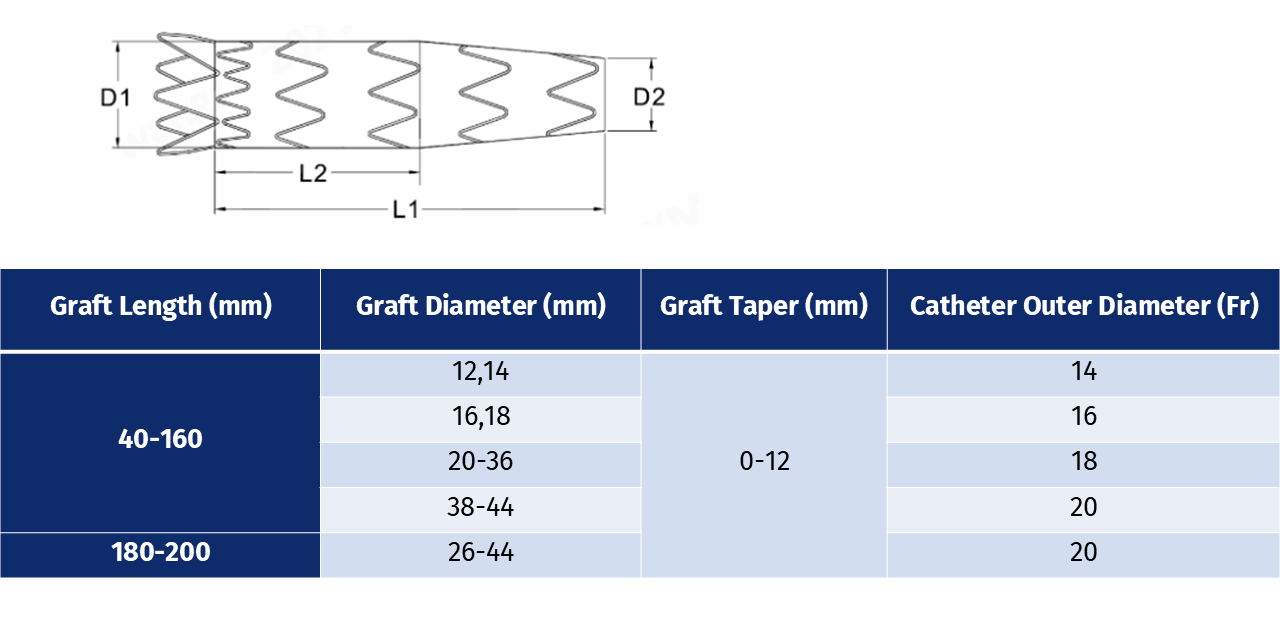

Specification Parameter